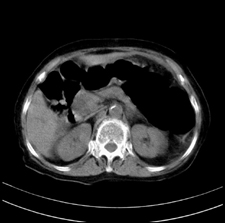

患者,女,75岁。腹痛,体黄5日,膝胸位时腹痛缓解。肝功能明日出来。彩超提示胆总管占位,未见血流信号。心电图提示s-t段改变。患者体质较弱,未能增强。

胆总管多发结石伴肝内外胆管轻度扩张。

胆总管上段,腔内有软组织密度影 ,ct值36-44hu。大家看有没有胆管癌的可能。

典型胆总管多发结石;增强扫描前后ct值是否发生改变是鉴别结石与占位的依据。

胆管没有鼠尾征,还是考虑结石